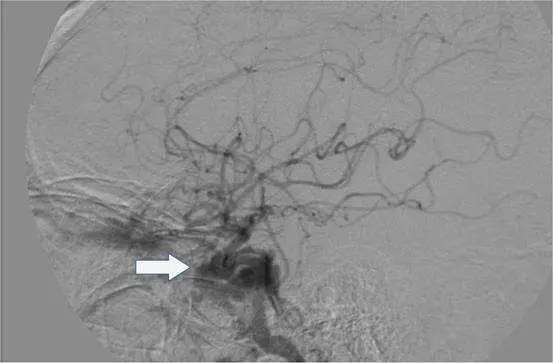

如附圖,病⼈外傷後之⾎管攝影顯⽰不正常的顱 內動靜脈 瘻管, 瘻管最可能引流的靜脈結構(箭號)為何?

本題考查外傷性頸動脈海綿竇瘻管(carotid-cavernous fistula, CCF)的血管攝影影像判讀,重點在於辨識動靜脈瘻管的靜脈引流目標結構。CCF 是動脈血液直接分流進入低壓靜脈系統(海綿竇)而不經過微血管床的異常連接,外傷性 CCF 幾乎均為直接型(Direct/Type A),由顱底骨折或加速-減速傷害造成頸內動脈(internal carotid artery, ICA)壁撕裂所致。

本圖為側位顱腦數位減影血管攝影(digital subtraction angiography, DSA)影像,可見腦部動脈樹顯影(動脈期)。白色箭號指向影像左下方顱底區域,位於蝶鞍(sella turcica)旁外側、中顱窩底部,可見一局部膨大、密度較高的異常靜脈結構,形態符合海綿竇(cavernous sinus)早期顯影的特徵——動脈期即出現的靜脈結構充盈,正是動靜脈瘻管的典型血管攝影表現(arteriovenous shunting)。箭號所指位置解剖上與海綿竇位置吻合:位於蝶骨體兩側、垂體窩(pituitary fossa)外方,介於眶上裂(superior orbital fissure)至岩骨尖(petrous apex)之間的顱底區域。